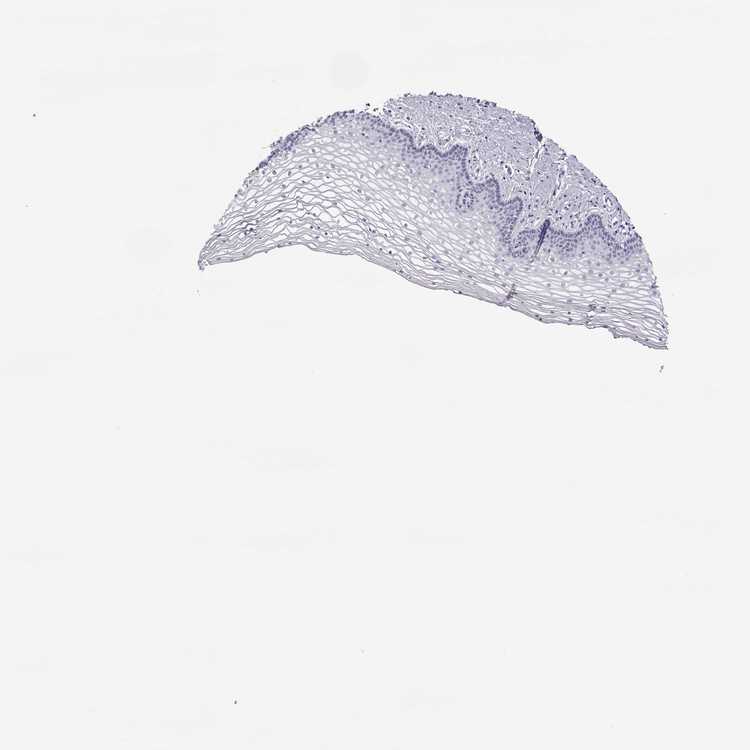

TISSUE PRIMARY DATA VAGINA Show tissue menu

VAGINA - Antibody stainingi

Antibody staining in the annotated cell types in the current human tissue is reported as not detected, low, medium, or high, based on conventional immunohistochemistry profiling in selected tissues. This score is based on the combination of the staining intensity and fraction of stained cells.

Each image is clickable and will lead to virtual microscopy that enables deeper exploration of all samples and also displays staining intensity scores, fraction scores and subcellular localization as well as patient and tissue information for each sample.

Antibody HPA046055Antibody HPA061884

Squamous epithelial cells Not detectedNot detected